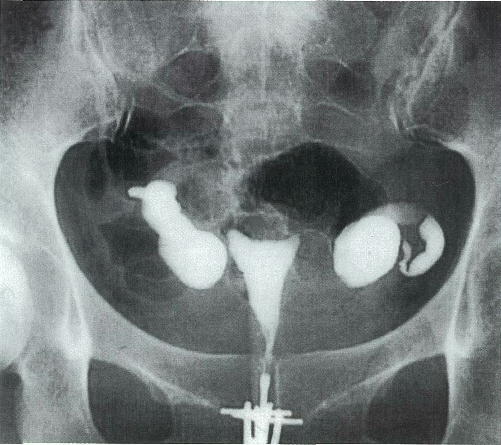

30歳の女性。挙児を希望して来院した。26歳で結婚し,避妊していなかったが妊娠に至らない。初経12歳。月経周期28日型,整。月経痛は認めない。24歳時,右卵管妊娠で卵管温存手術を受けた。身長 158cm,体重 45kg。子宮は正常大で,両側付属器は触知しない。基礎体温は2相性。血中ホルモン値(月経周期7日目):LH 4.8mIU/ml(基準 1.8~7.6),FSH 8.1mIU/ml(基準 5.2~14.4),プロラクチン 6.2ng/ml(基準 15以下),エストラジオール 34pg/ml(基準 11~230),プロゲステロン 0.2ng/ml(基準 0.5以下),テストステロン 42ng/ml(基準 30~90)。子宮卵管造影写真を別に示す。夫の精液検査所見:量 2.5ml,精子濃度 8×10^6/ml,運動率 55%,奇形率 15%。

診断 乏精子症,卵管留水腫